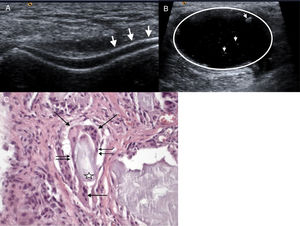

Caso clínicoVarón de 44 años, acudió al hospital por lumbalgia. Un año antes inició con lumbalgia progresiva e irradiación a miembro pélvico izquierdo. Seis meses antes presentó artritis de rodilla izquierda de inicio súbito, remitiendo con antiinflamatorios. El paciente se hospitalizó, su examen físico mostró marcha independiente, antiálgica, claudicación, disminución de la movilidad de columna por dolor, Lasegue y Bragard positivos, hipoestesia en dermatoma L5-S1 y RI con derrame articular. La biometría hemática, urianálisis, velocidad de sedimentación globular y proteína C reactiva con parámetros normales, ácido úrico sérico de 11,8mg/dl y ácido úrico en orina de 24h: 560mg. La radiografía con espondilolistesis lítica de L5, en la resonancia magnética (RM) señal hipointensa en T1 y heterogénea en T2 localizada en el espacio interespinoso de L4-L5, y en articulación facetaria izquierda que invade el neuroforamen izquierdo con lisis bilateral de la pars interarticular (fig. 1). El ultrasonido de rodilla izquierda mostró doble contorno del cartílago del cóndilo femoral medial (fig. 2A) y quiste de Baker de paredes gruesas con puntilleo hiperecoico en su interior (fig. 2B). Se efectuó laminectomía, liberación radicular de L5, fijación transpedicular L5-S1 y artrodesis postero-lateral. El estudio histopatológico del material removido por cirugía reportó material amorfo anfófilo acelular constituido por histiocitos epitelioides que fusionan sus citoplasmas formando células gigantes multinucleadas de tipo a cuerpo extraño (fig. 2C).

A) Imagen de doble contorno del cartílago femoral (flechas). B) Quiste de Baker de paredes gruesas (círculo) con puntilleo hiperecoico en su interior (cabezas de flechas). C) Material amorfo anfófilo acelular (estrella) bordeado por histiocitos epitelioides (doble flecha) y células gigantes multinucleadas (flecha) que fagocitan este material.